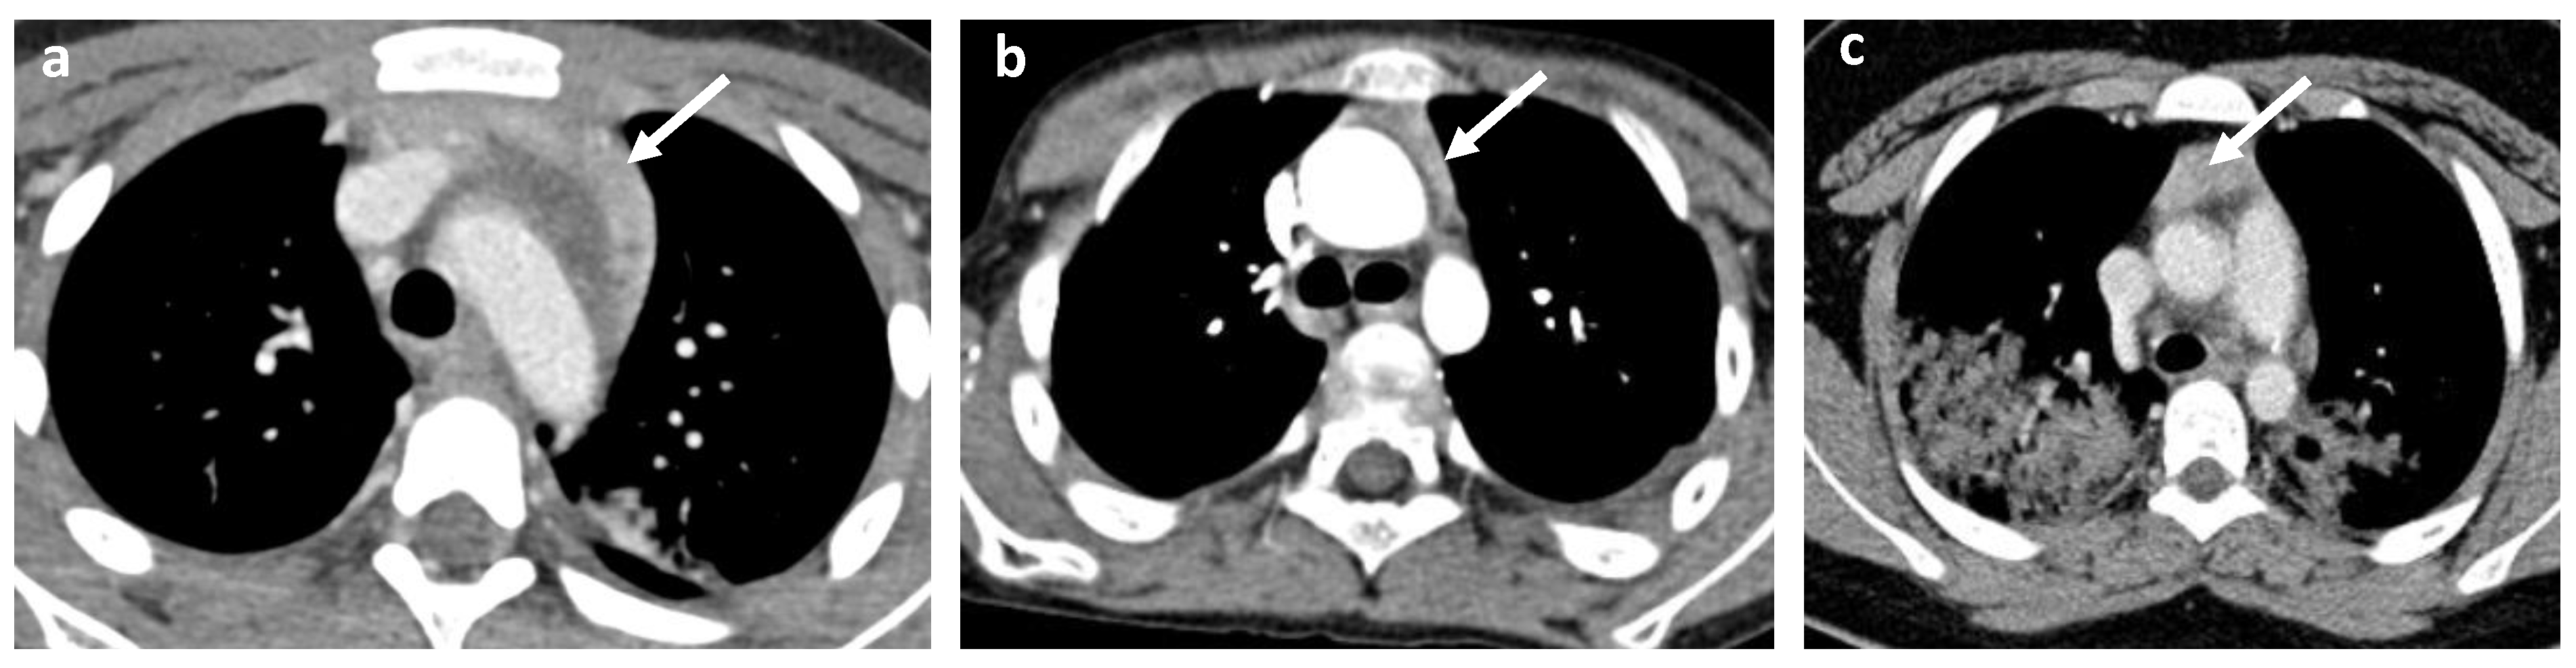

- Cervical, mediastinal, and axillary lymphadenopathy.

| Cervical lymphadenitis | 10 | 45.5% | 19.6% | |

| Mediastinal lymphadenitis | 4 | 18.2% | 7.8% | |

| Axillar lymphadenitis | 3 | 13.6% | 5.9% | |

| Thymic enhancement | 5 | 22.7% | 9.8% | |